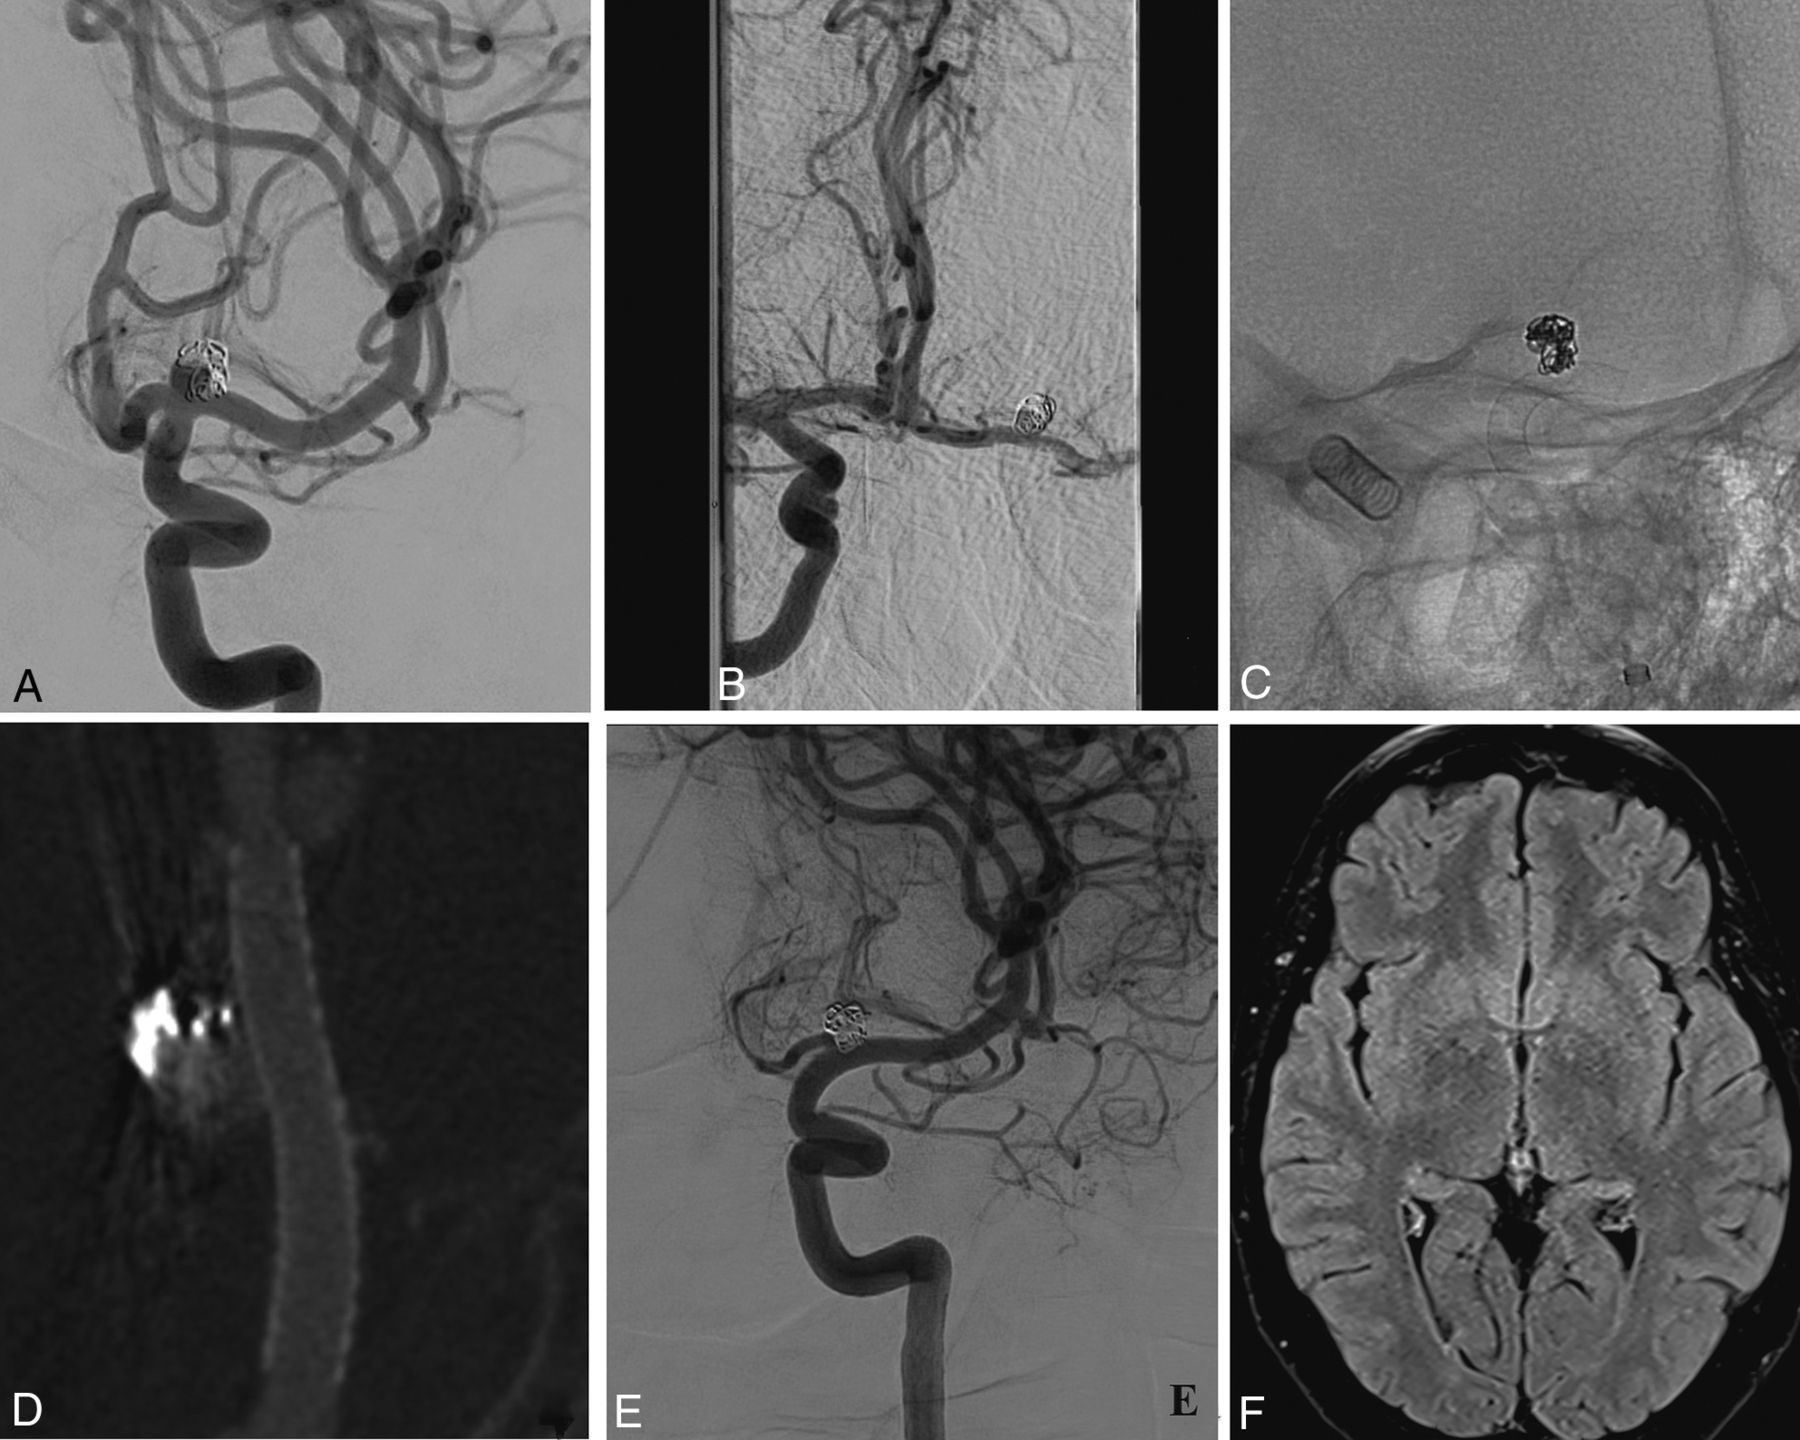

The mean angiographic follow-up was 13 months (range, 9–24 months). Complete occlusion (OKM D) was achieved among 19 medium-sized (95%) aneurysms (Figs 1 and 2). Incomplete occlusion (OKM B) was found in 1 very large aneurysm (5%). This incompletely occluded aneurysm was stable at the last angiographic follow-up. No cases of aneurysm rupture were reported. There were no cases of in-stent stenosis.

Patient 4. A, A right ICA angiogram (anterior-posterior view) shows a wide-neck medium-sized ICA terminus aneurysm. B, 3D reconstruction depicts a bilobate irregular shape of the aneurysm with the right A1 segment originating from the neck. C, Contralateral ICA angiogram demonstrates the patency of the AcomA with retrograde flow into the left ICA terminus segment. D, A 4.5 × 14 mm PED is deployed from the M1 (before the temporal branch) to the supraclinoid ICA, avoiding, as much as possible, the ostium of the ophthalmic artery. E, After 12 months, the aneurysm is completely occluded, and the right A1 shows absence of anterograde flow. The lateral lenticulostriate arteries and the temporal branch of the MCA are patent. F, The time-of-flight 3D reconstruction sequence shows absence of flow into the aneurysm (OKM D occlusion) and retrograde filling of the right anterior cerebral artery from the contralateral side through the AcomA.

Patient 8. A, The left ICA (frontal view) depicts a previously ruptured and recanalized medium-sized ICAbifA treated with coiling during the acute phase. B, The presence of contralateral filling from the AcomA. C, A PED, 3.5 × 12 mm, is successfully deployed covering the aneurysm and the left A1 segment. The PED was delivered before the origin of the M1 lenticulostriate arteries. D, Flat panel angiography confirms good vessel wall apposition of the stent. E, A 14-month angiographic follow-up shows complete aneurysm occlusion as well as flow remodeling of the covered A1 with narrowing but without any lesions on the FLAIR sequences (F).